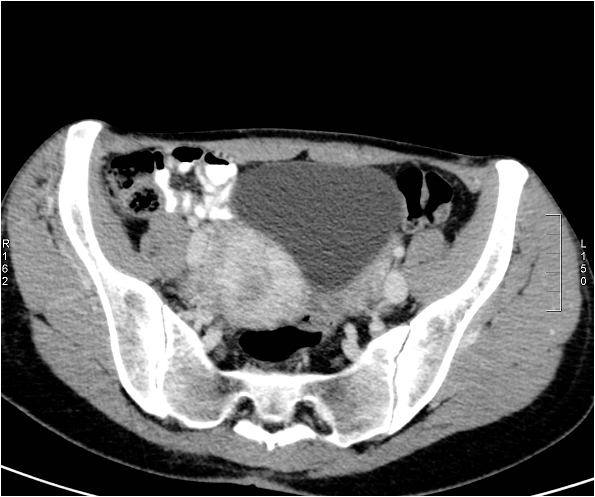

Image

Figure 9. Axial CT images show an extensive tumor in the bladder fundus.